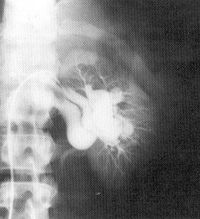

分泌性尿路造影可能会显示出部分或完全性肾功能衰竭。有时会发现一不规则的充盈缺损,或肾脏的扭曲变形、远端梗阻。多普勒(Doppler)超声检查是一种更加准确而无损伤的方法。数字减影血管造影是诊断该疾病的最有效而直观的重要手段。

肾动静脉瘘造影